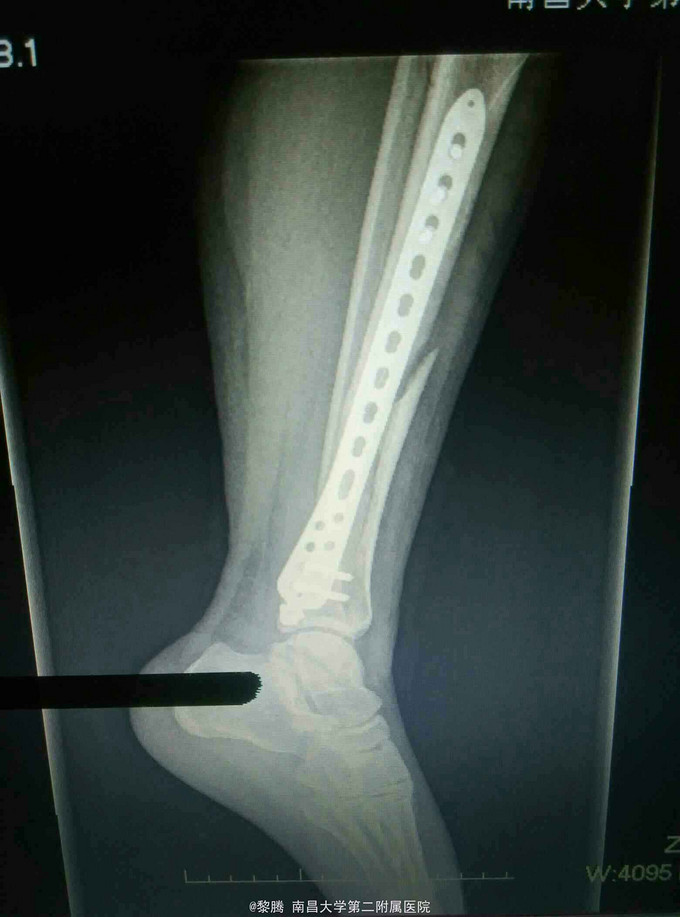

诊断:左胫腓骨骨折 治疗:胫骨骨折复位内固定

随访:术后3月患肢避免负重,定期复查。 讨论:患者行Mippo技术做骨折内固定,因行闭合复位,难以完全解剖复位,关键纠正旋转、成角,恢复正常力线。